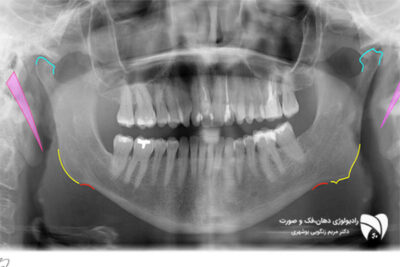

یکی از این تکنیکها، رادیوگرافی پانورامیک است که تصویری کلی از فکها و ساختارهای اطراف ارائه میدهد. این تکنیک بهخصوص در بیماران با محدودیتهای فکی بسیار مفید است. همچنین، دستگاههای قابل حمل تصویربرداری دهان امکان تصویربرداری در موقعیتهای خاص را فراهم کرده و نیاز به جابهجایی بیمار را کاهش میدهند. در کل، تکنیکهای پیشرفته تصویربرداری دهان به متخصصان کمک میکنند تا اطلاعات دقیقتری از مشکلات بیماران دریافت کرده و درمانهای بهتری ارائه دهند.

رادیوگرافی پانورامیک چیست و در چه مواردی استفاده میشود؟

رادیوگرافی پانورامیک روشی است که تصویری کلی از فکها، دندانها و ساختارهای اطراف را ارائه میدهد. این روش برای بررسی مشکلات گسترده، مانند شکستگیها یا بیماریهای استخوانی، بسیار کاربردی است و نیاز به باز کردن کامل دهان بیمار ندارد.